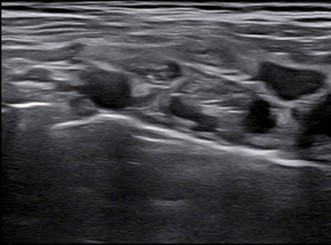

– Siêu âm hạch cổ: không phát hiện bất thường

Hình 9: Hình ảnh siêu âm hạch cổ: không phát hiện bất thường